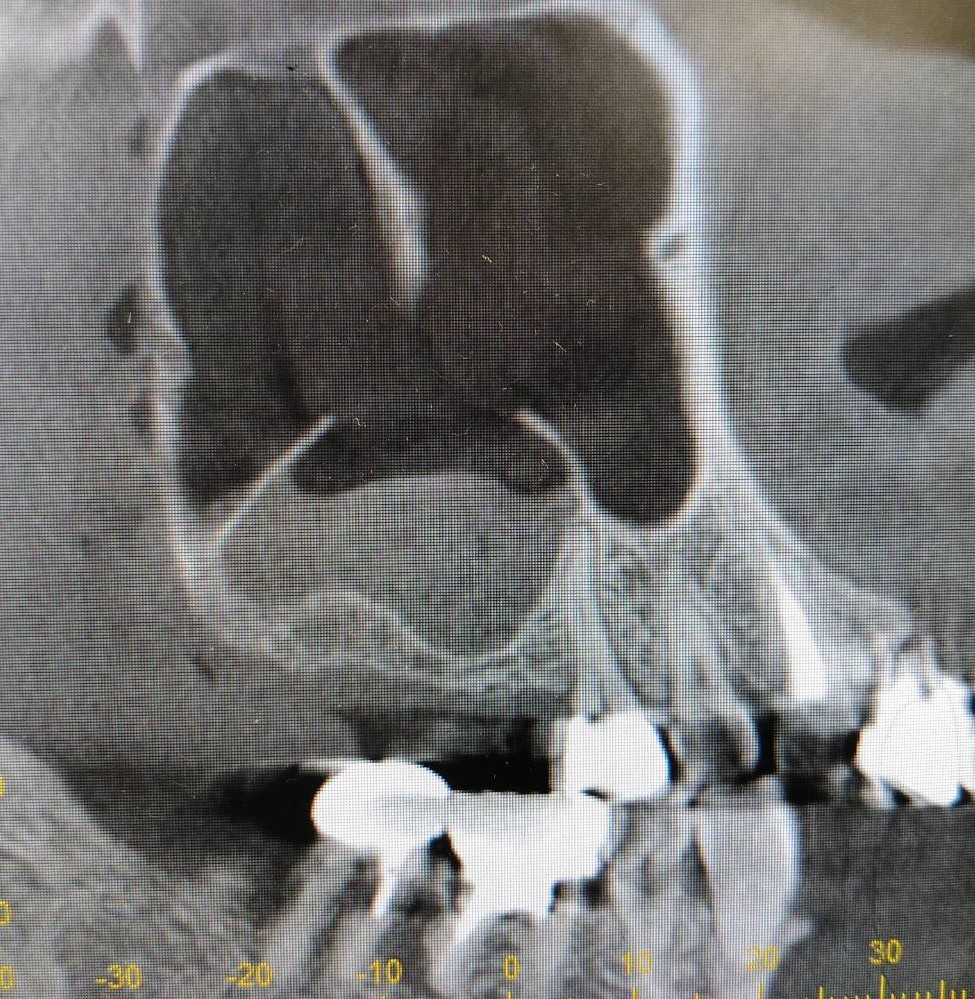

上顎洞底挙上術を併用したインプラント埋入の症例紹介

Before

After

6か月後

インプラント埋入

主訴

右上奥歯にインプラントを入れたい。

治療内容

右上奥歯の骨が薄いため、まず人工骨を用いて造骨しました。6か月後に骨ができたのでインプラントを埋入しました。

治療費

上顎洞底挙上術:165,000円(税込)

インプラント埋入術:220,000円(税込)

治療期間

7か月

通院回数

5回

想定されたリスク

※上顎洞粘膜穿孔、上顎洞炎、腫脹、内出血、鼻出血の可能性がありました。

石毛 俊作先生

大神宮デンタルクリニック

インプラントを埋入する際に十分な骨量がない場合は骨造成を行います。骨造成の方法は症例によって異なりますが、今回のケースは上顎洞底挙上術を用いました。